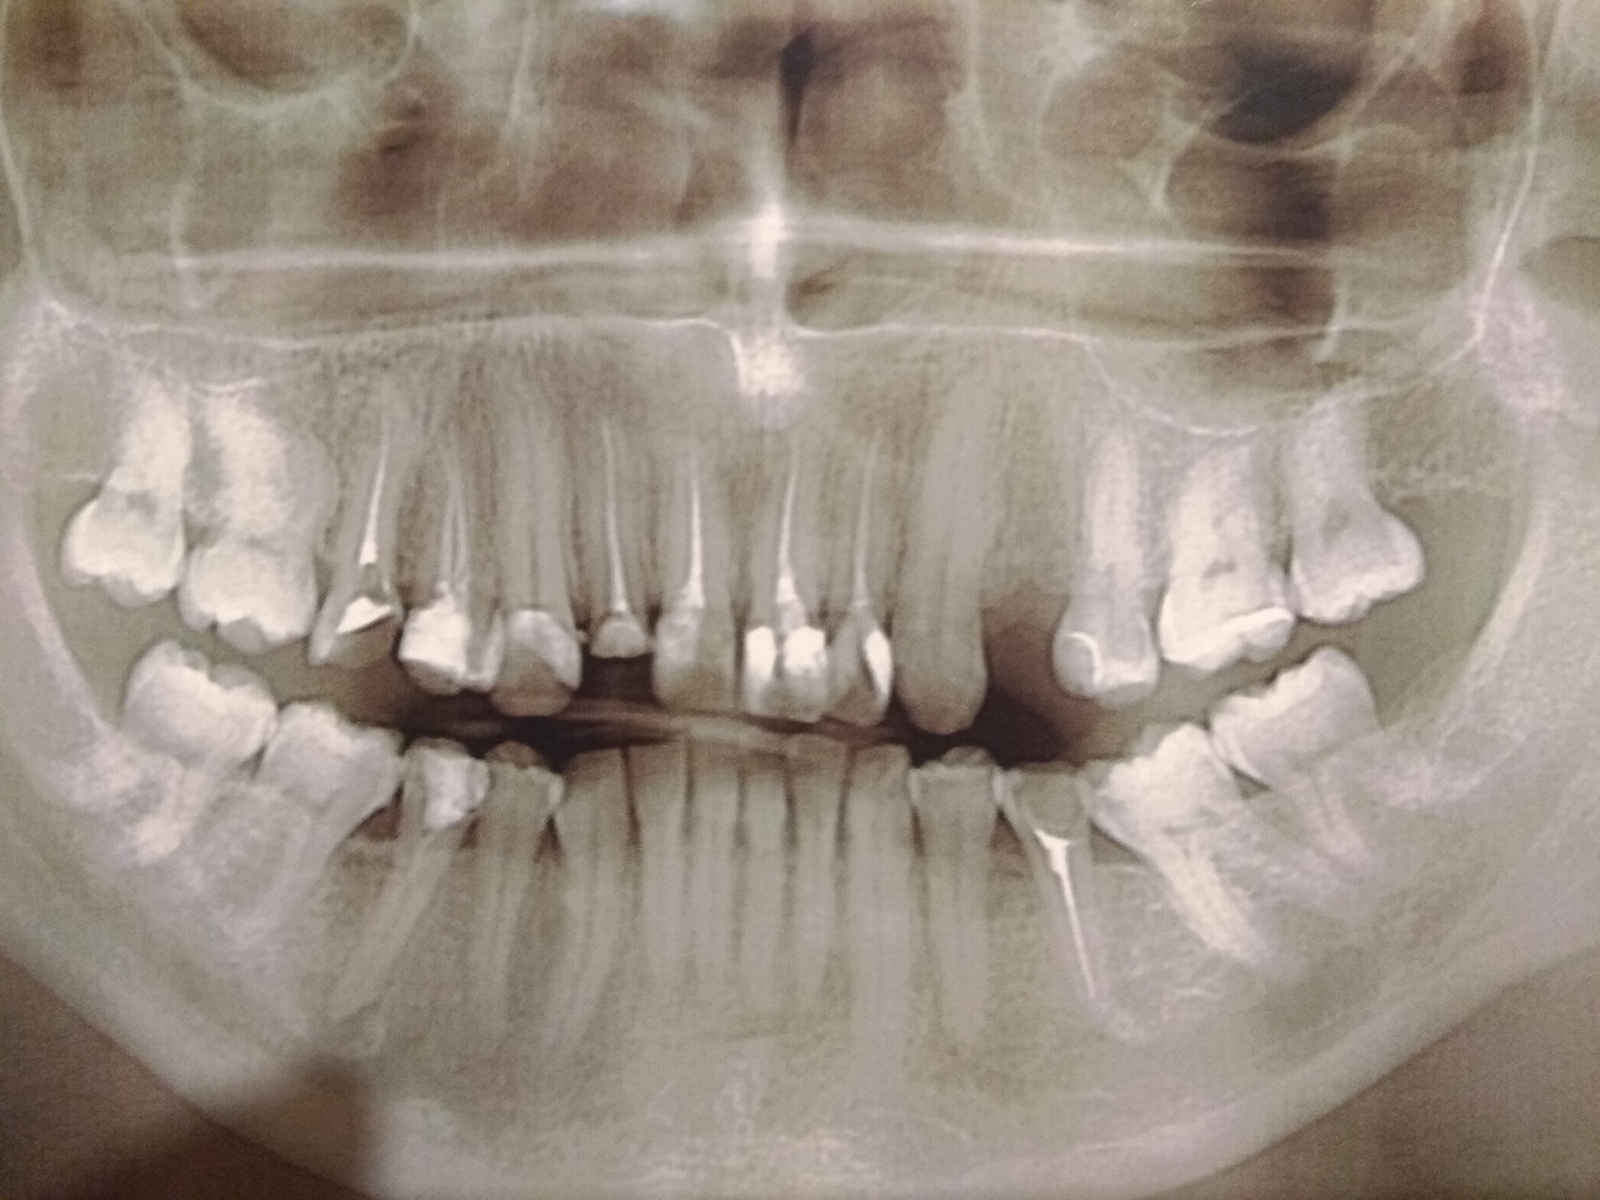

Сломался зуб, почти под самую десну.

На мои слова о том, что может сразу имплант ? Закатывают глаза "ну если вы так хотите, то можна и так" Но я же блин пришел к спецам. Если зуб был дважды пломбирован и сломался, то корни уже не лучшие.

В общем. Подскажите люди добрые. Если вы в теме. Прав я, в том, что не надо растягивать удовольствие на много серий. И сразу уже поставить имплант?